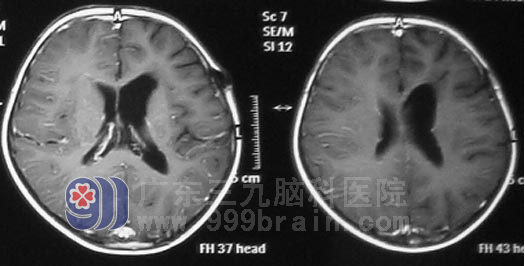

生殖细胞瘤为低度恶性肿瘤,对放射线非常敏感。小勇在 肿瘤综合治疗中心接受放射治疗。虽然肿瘤恶性程度相对较低,但生殖细胞瘤常呈浸润生长,极易向蛛网膜下腔及脑室系统种植、播散,故在头部治疗的同时,全脊髓接受预防照射的全中枢治疗。完成阶段性放疗后复查头部MR显示肿瘤明显缩小,头痛呕吐症状也基本改善,放疗结束后在行6周期化疗,小勇恢复情很好,没有出现头晕呕吐等不适症状。目前治疗结束已经2年半时间,复查头颅MR示情况良好,未见肿瘤复发。小勇已正常上学。

▲放疗后2年半